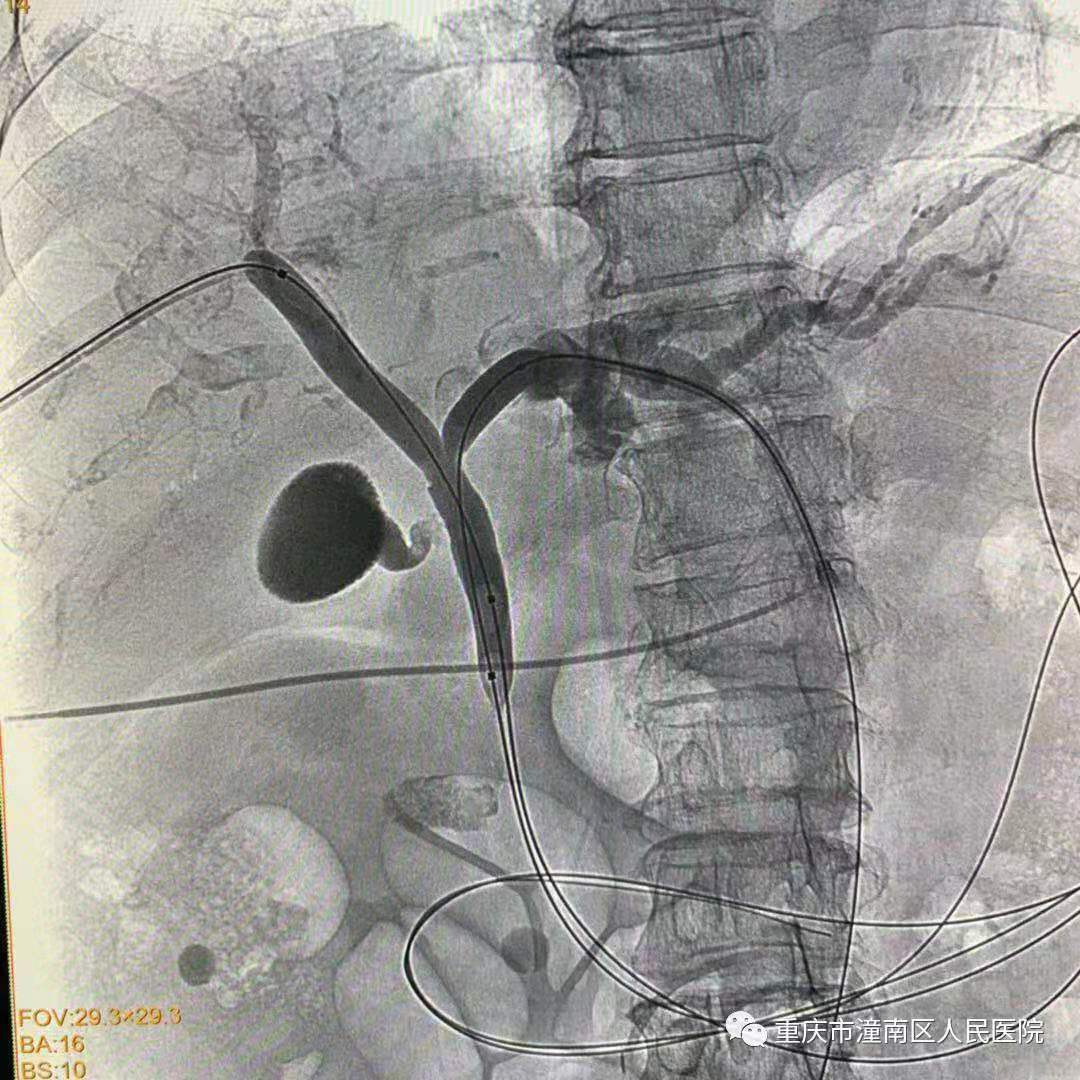

胡某,女,74岁,因肤黄、尿黄伴全身皮肤瘙痒入院,诊断为肝门胆管癌伴胆道恶性梗阻,已失去外科手术切除机会;为消除黄疸,减轻肝功能损害。小艾电竞社区 放射科、肝胆胰甲乳外科医生在重医附二院教授指导下,成功对该患者行“经皮经肝胆道内支架引流术”(EMBE),这是小艾电竞社区 在新建放射介入中心大型血管机(DSA)上开展的首例介入手术,也是潼南区首例,术后患者胆道梗阻解除,双侧胆道引流通畅,现已回肝胆胰甲乳外科继续治疗。